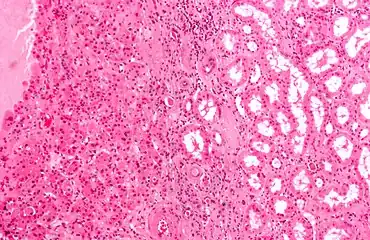

Micrograph of a renal oncocytoma. H&E stain. -

An oncocytoma is an epithelial tumor composed of oncocytes, large eosinophilic cells having small, round, benign-appearing nuclei with large nucleoli and excessive amounts of mitochondria.